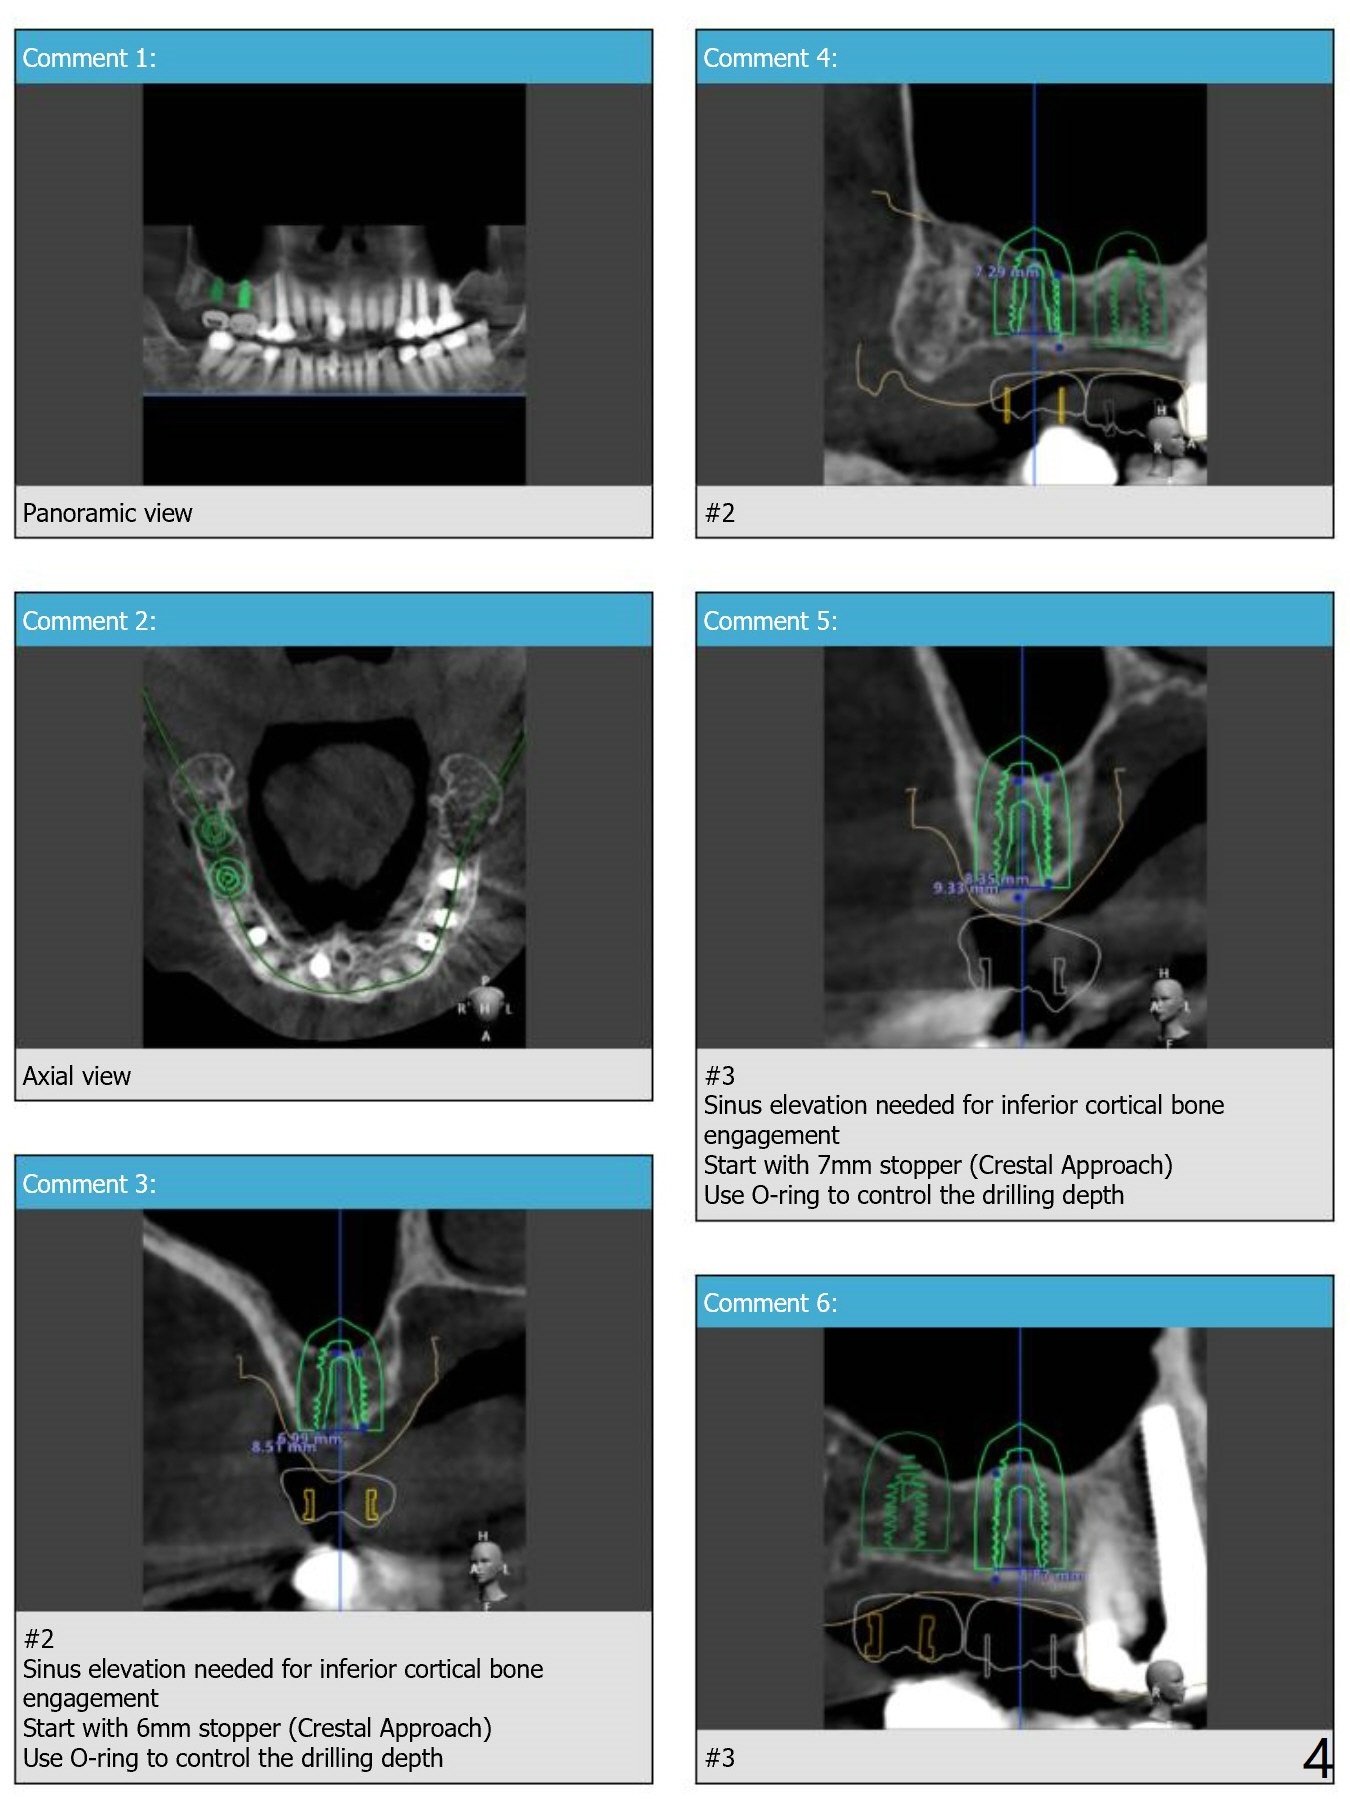

For short bone, Neo Navi drills are longer than they are supposed to be. Depth will be controlled by using O-rings. For example use an O-ring at the first mark as a stopper so that we do not have to take a good look while drilling (Fig.6,7). From that one, use 2 O-rings for the rest of way. As mentioned earlier, remove surgical guide for sinus lift (Sinus Master Kit). Replace the guide for implant placement. Note that tap drill is not needed, because of the soft bone in the posterior maxilla. Review Fig.1-5 for design, especially stopper for sinus lift at #2 and 3.